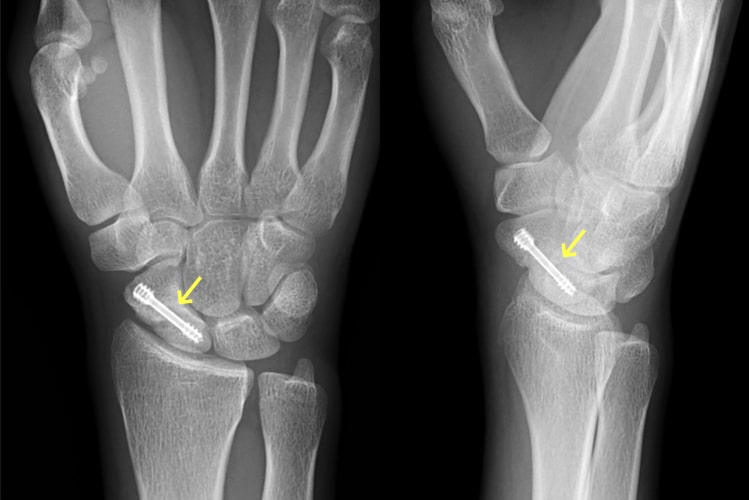

舟状骨骨折

舟状骨骨折写真

舟状骨骨折後偽関節

舟状骨骨折術後写真

骨移植併用内固定術後

原因

スポーツや事故で手をついて転倒することで生じます。舟状骨骨折は通常のレントゲン写真で分かりづらいことも多く、専門医でないと見落とすこともあります。手首の痛みが残る場合は舟状骨骨折を疑って多くの方向からレントゲン写真を撮ったり、CT撮影をする必要があります。

症状

腫れや痛みなどの症状が軽いため、整形外科への受診が遅れたり、手首の捻挫や打撲として診断されてしまっていることがあります。

治療方針

直後で骨折部のズレが少なければギプスで治療することも可能です。しかし、骨折部のズレが大きければ手術となります。また、長期間放置されて骨折部が治らないままとなったり(偽関節)、それに伴って関節の軟骨が摩耗した場合(変形性手関節症)は侵襲の大きな手術が必要となります。